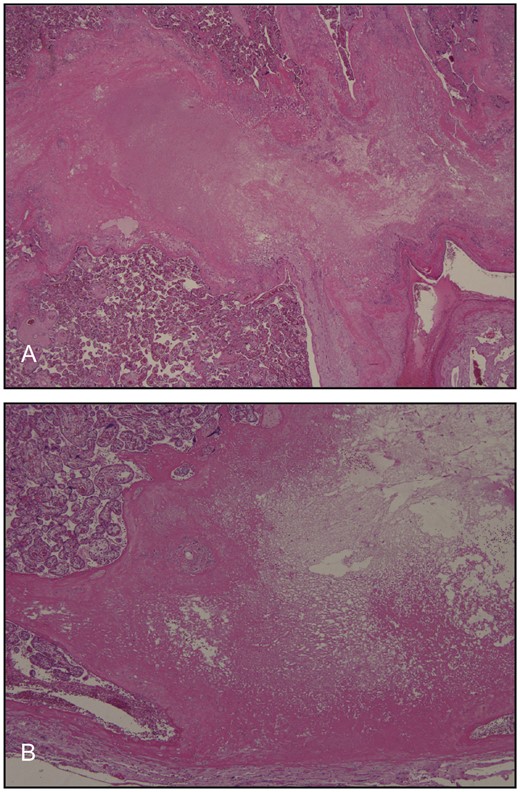

Microscopy confirmed the presence of focal infarcts, but no massive fibrin depositions were seen (Fig. 3A and B). There were no particular vascular abnormalities or apparent thrombi were detected. The placental villi were of appropriate maturity for gestational age and the villous vessels showed no structural abnormalities (Fig. 4A). No signs of chorioamnionitis were detected (Fig. 4B). No signs of funisitis or structural abnormalities were identified in the umbilical cord, which had two arteries and one vein (Fig. 4C). Using immunohistochemistry, the villi showed minimal immunoreactivity for complement split product C4d (Fig. 5).

Microscopic images of the villous structures. The villi were of appropriate maturity for gestational age and the villous vessels showed no structural abnormalities (A). Histopathology revealed no signs of chorioamnionitis (B) or funisitis (C).